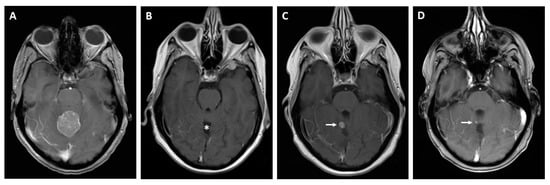

Figure 8.

MRI scan before and after neurosurgery in a 46-year-old patient with a large histologically proven CRC metastasis in the vermis, prior to (A) and after neurosurgery (B) (asterisk: resection defect). Recurrence of a small local tumorous lesion (C) (arrow) 12 months later. Significantly declining tumor nodule after chemotherapy (D) (arrow).